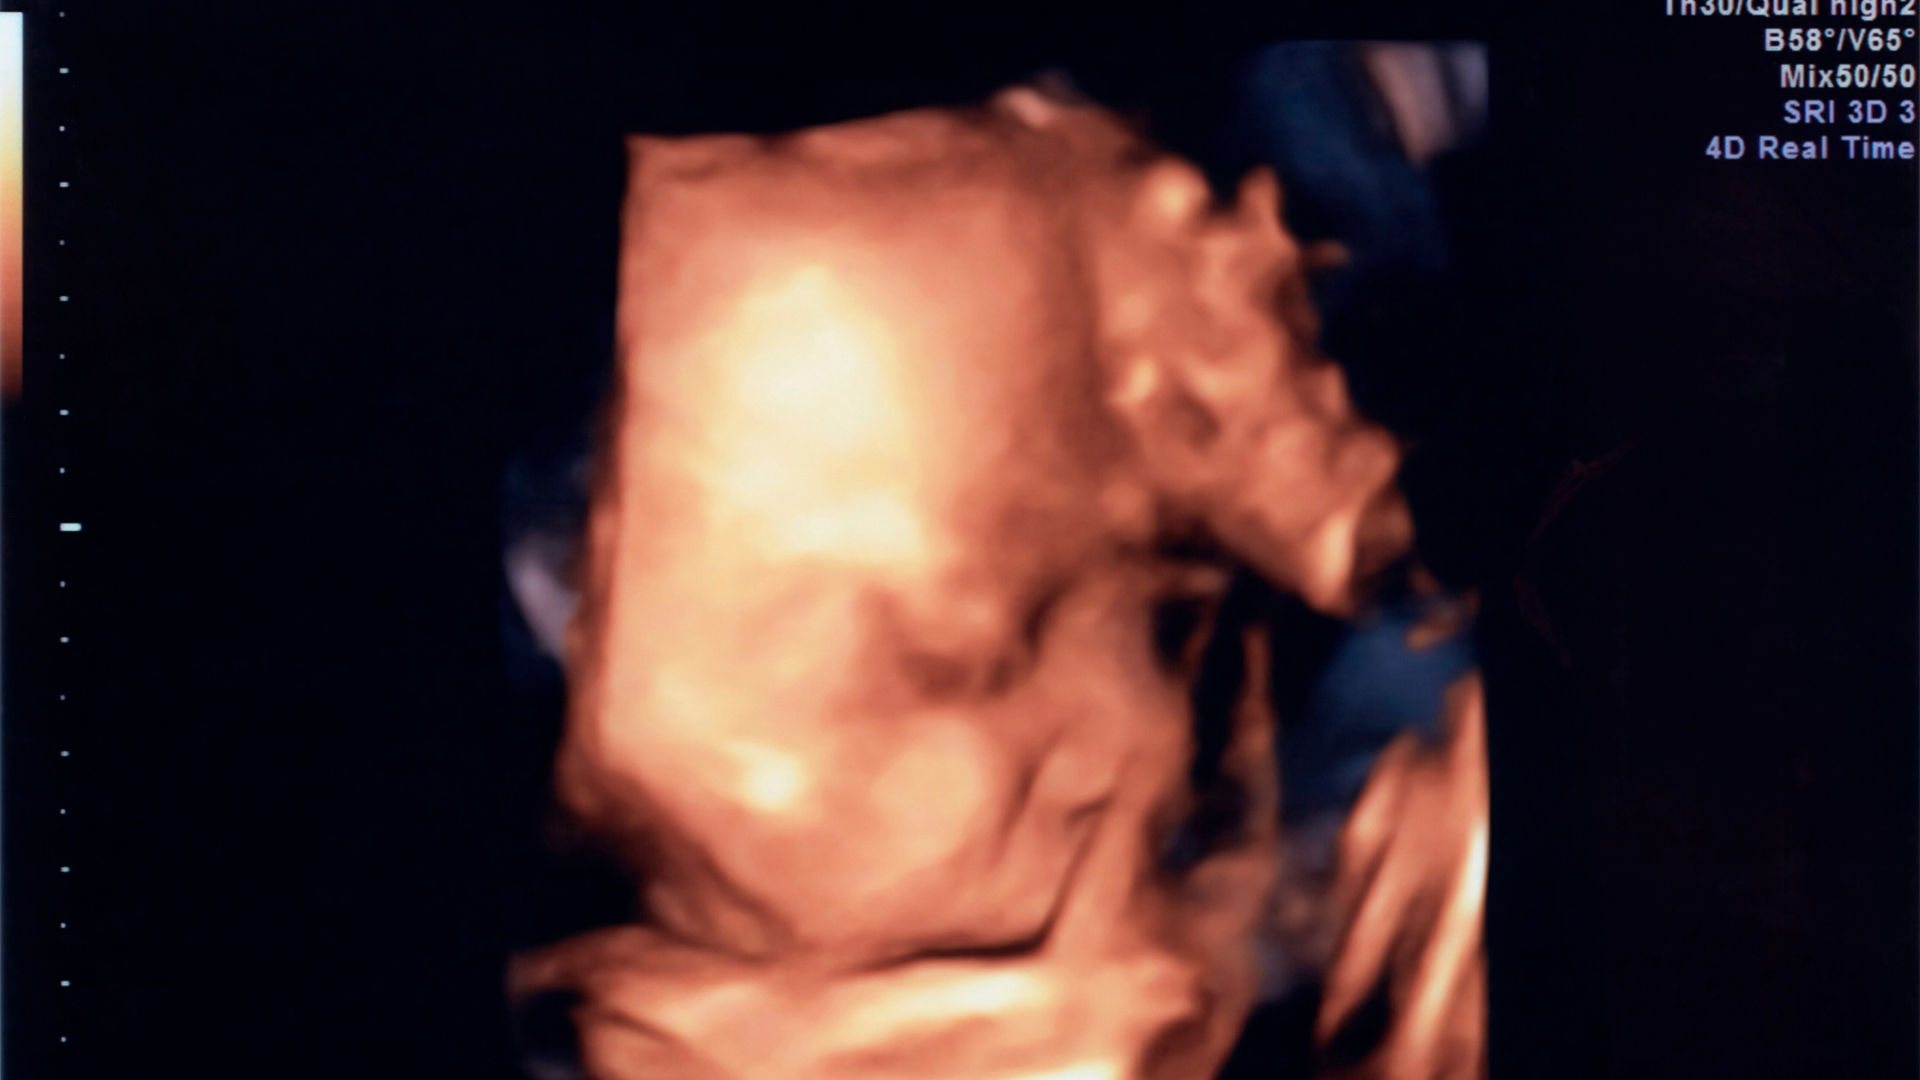

Siêu âm 2D, 3D, 4D khác nhau thế nào trong phát hiện hở hàm ếch?

- Siêu âm 4D: Cho phép quan sát chuyển động thời gian thực, hỗ trợ đánh giá cử động miệng và khuôn mặt.